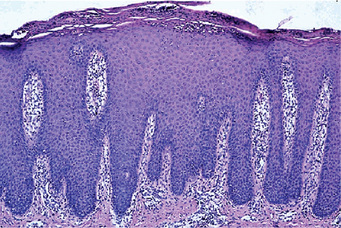

The microscopic appearance of psoriasis is characterized by uniform parakeratosis, absence of the stratum granulosum and elongation and clubbing of the rete pegs (Figs. 19-8, 19-9). The epithelium over the connective tissue papillae is thinned, and it is from these points that bleeding occurs when the scales are peeled off. Tortuous, dilated capillaries extending high in the papillae are prominent. Intraepithelial microabscesses (Monro's abscesses) are a common but not invariable finding; they are reported by Pisanty and Ship to be absent in oral psoriasis (Fig. 19-10). Mild lymphocytic and histiocytic infiltration of the connective tissue is also typical, particularly perivascular and periadnexal in location.

The disease is misnamed, since the changes are not restricted to the hair follicles. The characteristic findings in skin lesions are hyperkeratosis, papillomatosis, acanthosis and a peculiar benign dyskeratosis. This benign dyskeratosis is characterized by rather typical cells called corps ronds and grains. The corps ronds are larger than normal squamous cells and have a round, homogeneous, basophilic nucleus with a dark eosinophilic cytoplasm and a distinct cell membrane. These are found usually in the granular layer and superficial spinous layer. The grains are small, elongated parakeratotic cells situated in the keratin layer. Both corps ronds and grains represent partially keratinized cells and are found also in the typical slit-like intradermal vesicle just above the basal layer of cells, the typical suprabasilar cleavage. Acantholytic cells are commonly found floating in the lacunae produced by this intraepithelial separation. The microscopic features of the oral lesions are identical except that the hyperkeratotic changes are generally not pronounced.